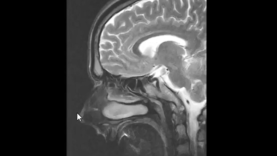

Neuroscience Basics Human Brain Anatomy and Lateralizat Mediube Subscribe Subscribed 3 1173 videos 0% 14 Views 0 Likes 2024-08-06 Neurologyneuroanatomy By Mediube 0 Comments (بازدید 14 بار, بازدیدهای امروز 1 ) Show more PREV Brain Anatomy Review and Quiz Mediube 2024-08-06 NEXT Introduction to Neuroanatomy Learn the Basics Neuroanat Mediube 2024-08-06 You might be interested in 0 How to do a lumbar puncture Mediube 2024-02-24 0 Alzheimer Mediube 2024-05-29 0 What is a seizure؟ Mediube 2024-05-01 0 Basic Parts of the Brain Mediube 2024-11-16 0 Doctor s Guide to Post Herpetic Neuralgia Chronic Nerve Pain Mediube 2025-11-02 0 Anatomy of the Brain Model Mediube 2024-08-05 0 Neurologic Examination: Reflexes Mediube 2024-03-16 0 Neuroscience Basics Human Brain Anatomy and Lateralization of B Mediube 2024-11-23 0 2-Minute Neuroscience- Benzodiazepines Mediube 2024-05-01 0 Upper Limb Neurological Examination – OSCE Guide (old version) _ UKMLA _ CPSA Mediube 2024-10-14 0 Introduction to Neuroanatomy Learn the Basics Neuroanat Mediube 2024-08-06 0 What is Multiple Sclerosis Mediube 2024-08-17 LEAVE YOUR COMMENT Cancel replyYour email address will not be published. Required fields are marked * Save my name, email, and website in this browser for the next time I comment. Δ